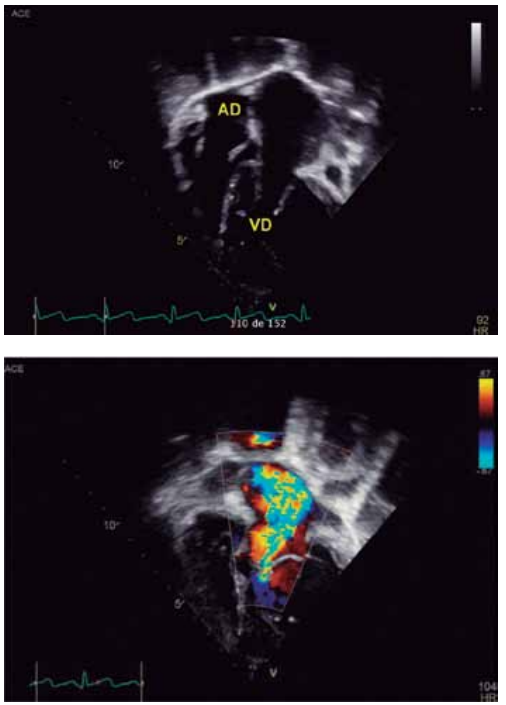

Para responder à questão, considere as imagens

ecocardiográficas a seguir, de uma criança de 12 anos, com

cardiopatia congênita.

Dados: AD = átrio direito; VD = ventrículo direito.

(Arquivo pessoal; imagens usadas com autorização)

Levando-se em consideração que o paciente apresenta concordância ventrículo-arterial, qual é o diagnóstico da cardiopatia congênita segundo as imagens apresentadas do ecocardiograma?